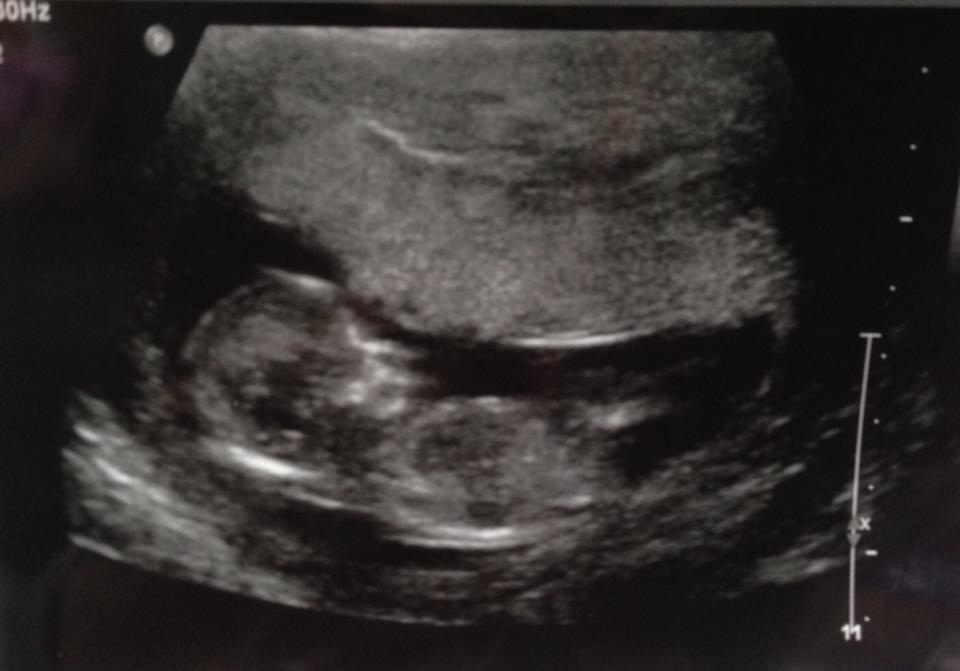

Here is photo of my little one at 13 weeks:

Attachment 8865